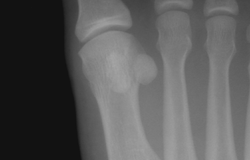

Sesamoid bones at the distal end of the first metatarsal.- First metatarsal bone.Deep dissection.

- Sesamoid bones at the distal end of the first metatarsal, left foot of an adult woman.